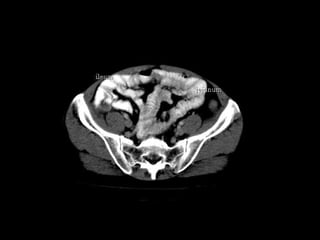

Radiographers use medical imaging equipment like X-rays and MRIs to produce images of patients' internal structures and organs. They are responsible for positioning patients, operating scanning machines, and ensuring quality images. Radiographers must have strong attention to detail, excellent communication skills, and the ability to work well under pressure to accurately capture anatomical features and diagnose any abnormalities.